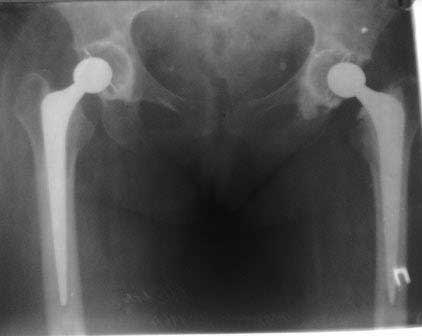

Если не ошибаюсь, то у больной имеется нестабильность бедренного компонента эндопротеза. Стартовые ("помповые") боли, а также зона просветления вокруг цемента и смещение цемента относительно кости...

Здравствуйте! К сожалению, качество рентгенснимков очень низкое,трудно определить есть ли разряжение на границе цементная мантия-кость.

Здравствуйте. Несомненно качество снимков не позволяет определить зону демаркации (если она есть). Делать нагрузочные снимки не вижу смысла, так как объем миграции может мыть незначительным и "на глаз" не определяться. При наличие же значимой (видимой) нестабильности всегда будет выраженная зона демаркации кость-цемент. Имеет смысл сравнить снимки сразу после имплантации и на данный момент. Обнаруженная миграция ножки может быть косвенным признаком возможной нестабильности. Впрочем, насколько я знаю, допускается некоторое "проседание" ножки при безцементом и цементом протезирование с отсутствием болевого синдрома (по типу вторичной фиксации). А вот миграция+боль, почти всегда= нестабильность.